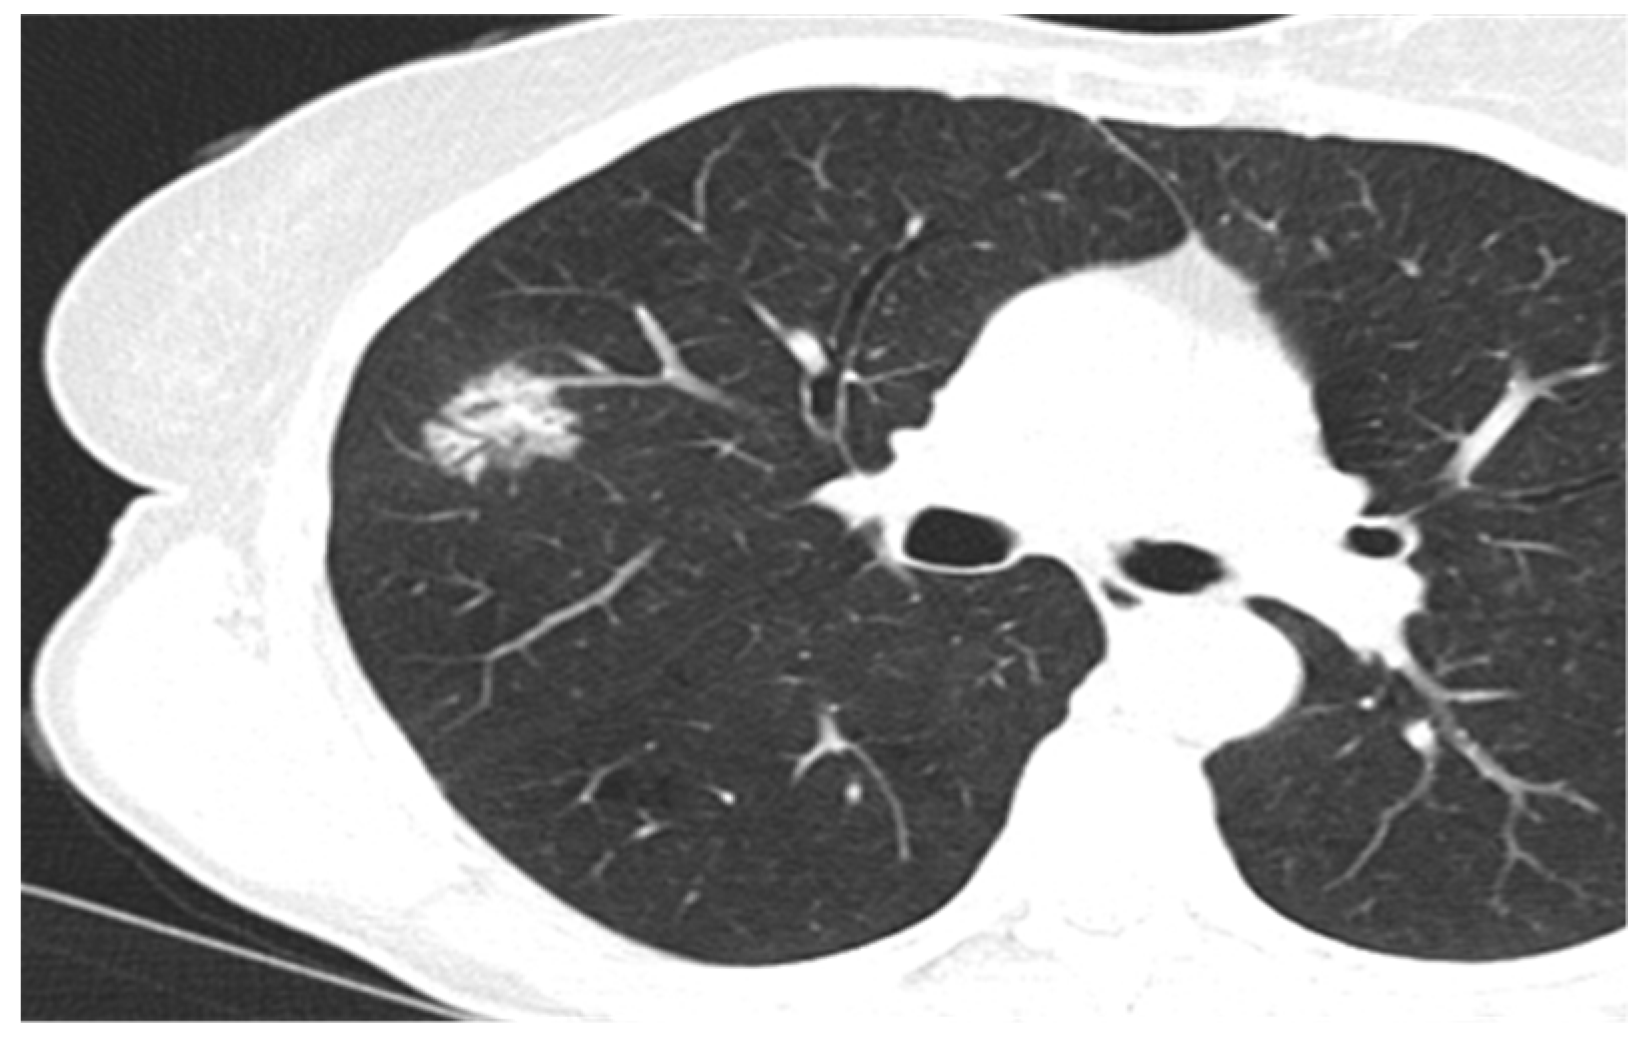

3. Results